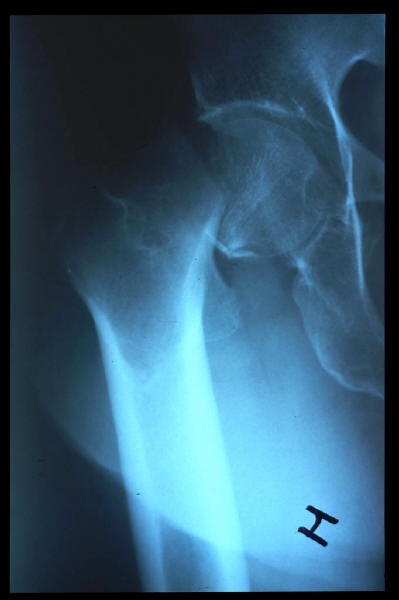

Fractura impactada de húmero .

Fractura de cuello de fémur